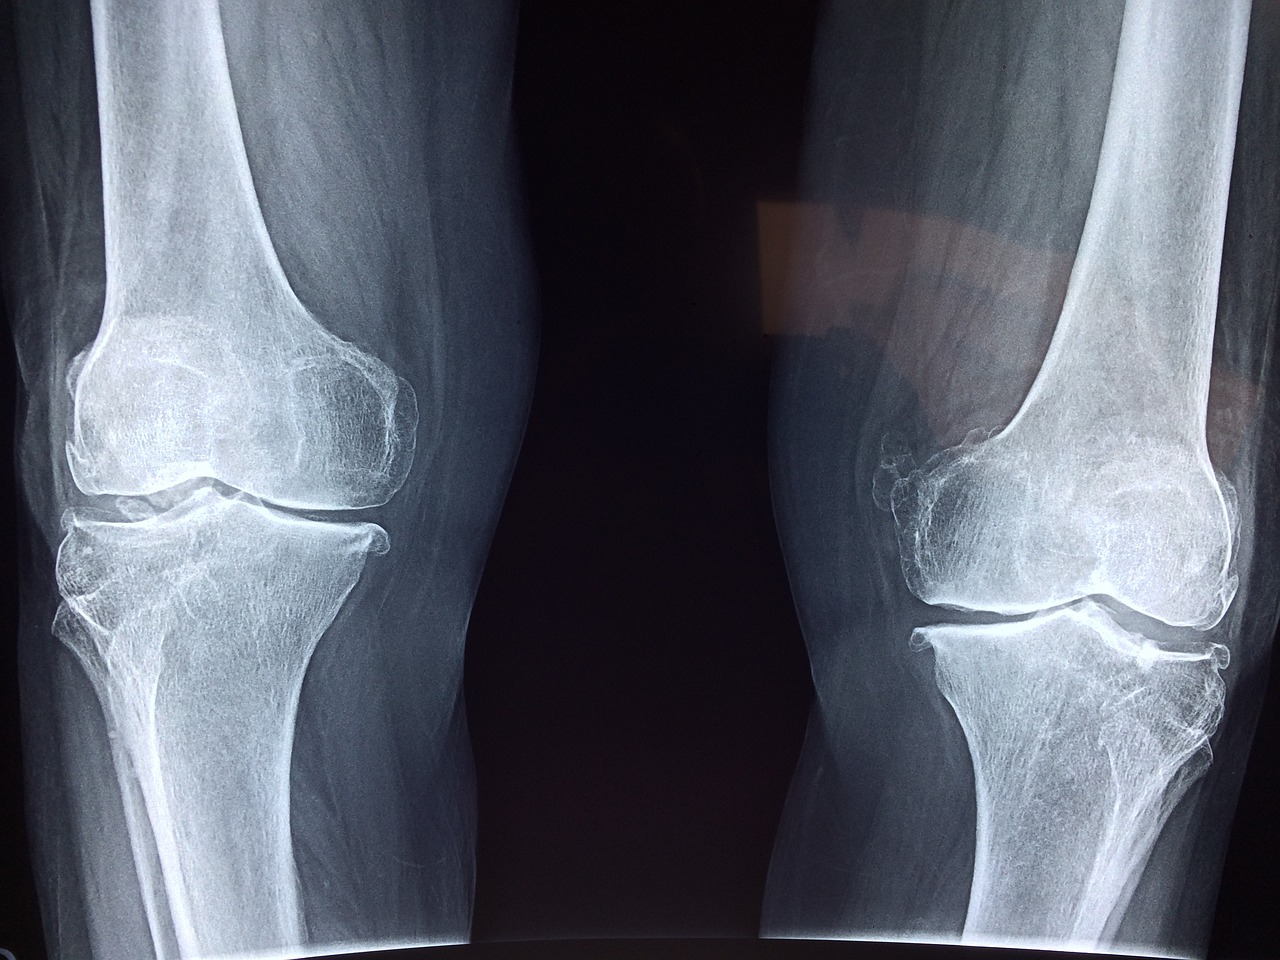

퇴행성 관절염일 경우

퇴행성 관절염은 말 그대로 노화로 인해 생기는 병으로 뼈의 관절면을 감싸고 있는 관절의 연골이 마모되어 생기는 병입니다. 관절 주변에 활액막에 염증이 생기고 이 염증이 치료되지않을 경우 통증이 심해지면서 물이 차기도 합니다.

이럴 경우 체중을 줄이고 근육량을 늘려주는 운동이 필요합니다.